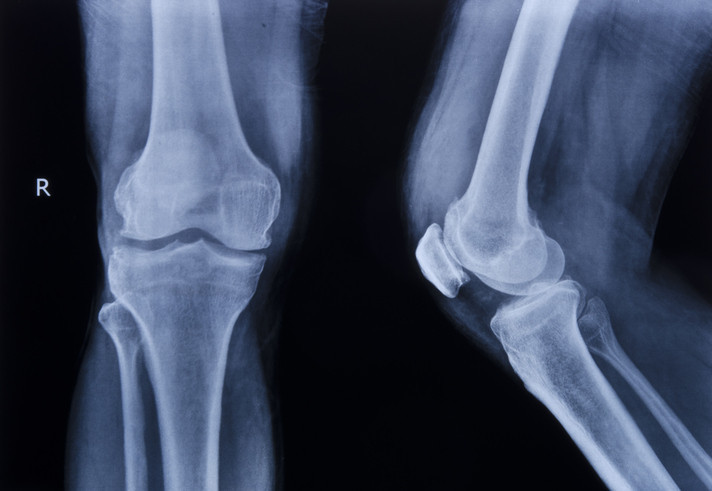

Kemik uzatmanın, kemiğin kendi iyileşme mekanizmasını kullanarak gerçekleştirildiğini belirten Prof. Dr. Kara, “Kemiği kestikten sonra günde yaklaşık 1 milimetre uzatma yaptığınızda vücut kendi yeni kemik dokusunu oluşturmaya başlıyor.

Bu yönteme ‘Distraksiyon Osteogenezisi’ deniyor. Özellikle boy kısalığı olanlarda, travmatik yaralanma sonrası kemikte kısalık gelişmiş hastalarda veya doğuştan kemik kısalığı bulunan kişilerde bu yöntem oldukça etkili” dedi.

Prof. Dr. Kara, kemik uzatma yöntemlerinin sadece estetik amaçlarla değil, aynı zamanda sağlık sorunları nedeniyle de uygulandığını vurguladı. “Travmatik yaralanmalar, enfeksiyon tedavisi sonrası kemik kaybı veya deformite gibi durumlarda hastanın hem uzatma hem de deformite düzeltme ihtiyacı olabilir. Bu gibi durumlarda kemik uzatma yöntemleri önemli bir çözüm sunuyor” diye ekledi.